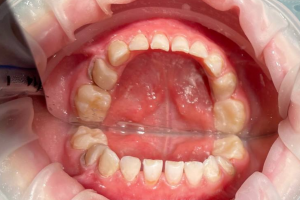

Семейная областная стоматология "Кидди Дентал" - это команда компетентных врачей, каждый из которых знает и любит свое дело. Опыт наших врачей, использование современного оборудования и надежных материалов позволят проводить лечение любой сложности.